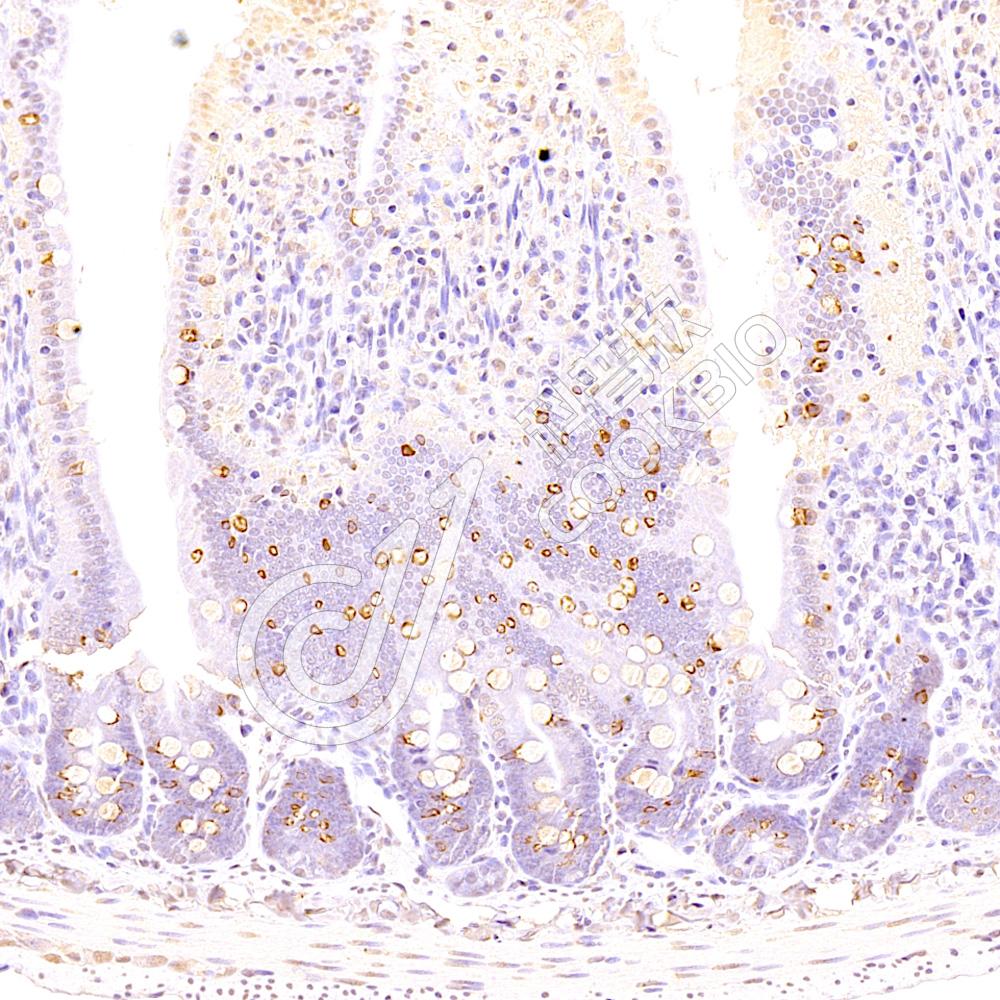

IHC检测LAMP1蛋白(货号 K1338847).

样品: 小鼠小肠, 4%多聚甲醛 (货号KSG1101) 固定12-24小时.

抗原修复: 柠檬酸抗原修复液(干粉, pH 6.0) (KSG1201), 98℃, 20分钟.

—抗: 1: 800稀释, 4℃ 孵育过夜.

二抗: S-vision免疫组化多聚二抗(山羊抗兔),即用型 (货号KB3906), 室温孵育20分钟.